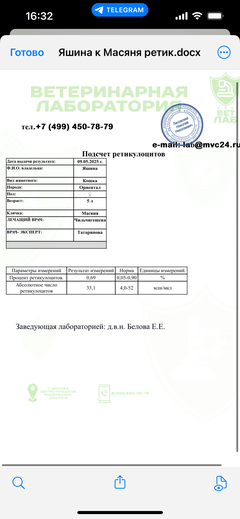

Была куплена в питомнике взрослой. У Масяни начались проблемы с кишечником и она стала подтекать и все пачкать. Надо отдать должное хозяевам - ее обследовали вдоль и поперек - как говорили местные врачи, сдавали много анализов но диагноза так и не поставили.

Ярко выраженная болезненность в области крестца, на обезболе полегче. По результатам приема невролога проведена миелография - множественная компрессия, возможно опухоль, возможно грыжа, нужно удалять...